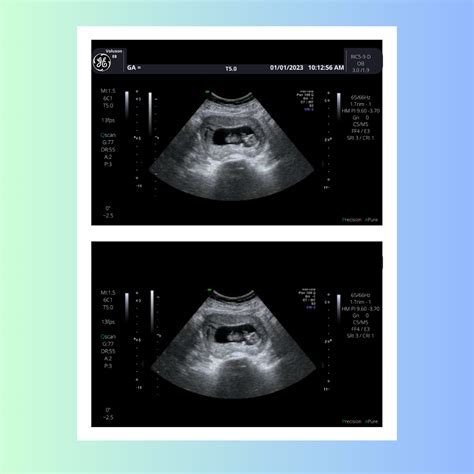

Interpreting the Results of a 6 Week Ultrasound

The results of a 6 week ultrasound provide valuable information about the early stages of pregnancy. Here are some key findings to look for:

• Gestational Sac: The presence of a gestational sac confirms the pregnancy. It appears as a small, fluid-filled structure within the uterus.

• Yolk Sac: By week 6, a yolk sac may be visible. This structure provides early nutrition to the embryo and is a positive sign of a healthy pregnancy.

• Fetal Pole: The fetal pole is the earliest visible structure of the embryo. It appears as a small, curved line within the gestational sac.

• Fetal Heartbeat: A fetal heartbeat may be detectable by week 6, although it is more commonly seen by week 7. The heartbeat appears as a flickering motion on the ultrasound screen.